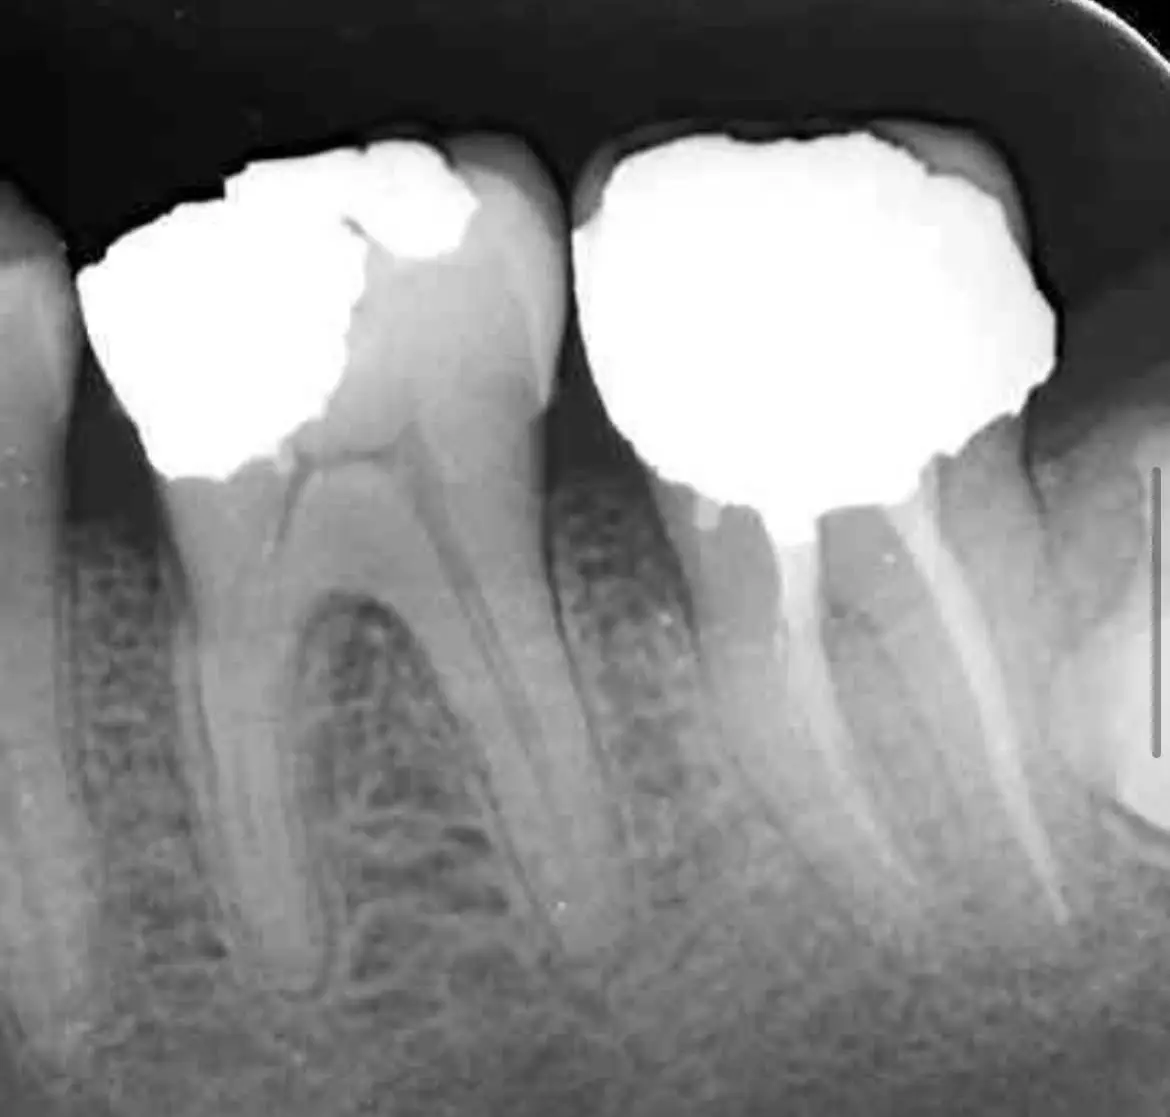

See the Difference Specialist Care Makes

Compare real treatment results through detailed before-and-after X-rays, showing how expert care restores dental health, precision, and long-term outcomes.